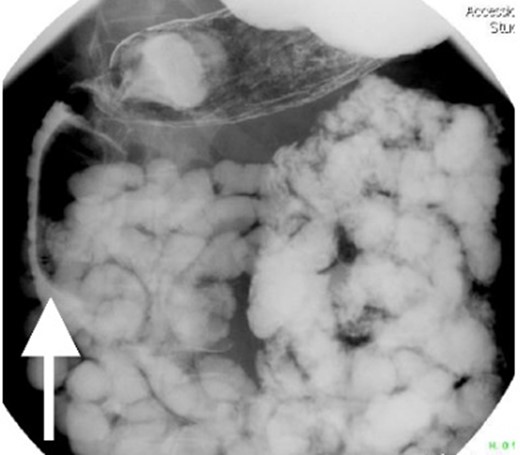

With regard to diagnostic workup, the literature has described cases with similar results to ours. Small bowel contrast studies frequently show smooth-walled polypoid filling defects within the duodenal bulb, and CT imaging is useful for delineation of adjacent structures including the common duct and pancreas [1]. Moreover, similar to the pathological results found in our patient, upper endoscopy biopsies are often equivocal as they are submucosal-based lesions [1]. The most useful diagnostic study, however, is endoscopic ultrasound, which may help distinguish the consistency and bowel layer of origin [2, 6], which unfortunately was not available at our institution.